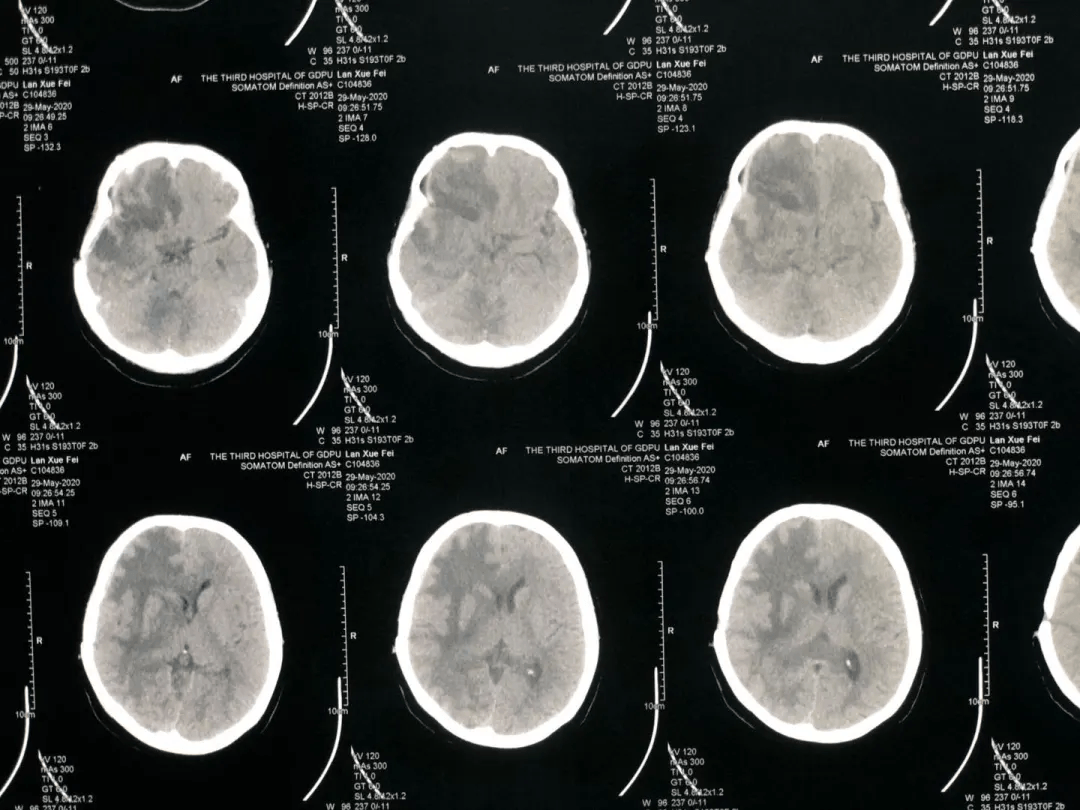

术前MR+CT片,显示巨大的复发肿瘤

患者蓝女士今年32岁,一年前在当地医院就诊发现脑部占位后,行右额颞叶低级别星形细胞瘤切除术,并结合化疗和放疗诊治,病程好转。但今年5月,患者头晕头痛明显,在当地医院复查时,考虑有肿瘤复发的情况。蓝女士通过朋友询问,立马辗转到广东药科大学广州复星禅诚医院,找到肿瘤五科主任罗鹏飞教授,目的是降颅压和得到肿瘤精准治疗。